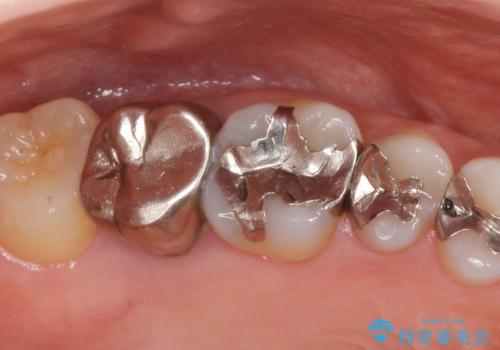

「状態の悪い銀歯がなくなりすっきりした」と喜んで下さいました。

見た目や使用感にご満足頂き、他の部位も現在治療中です。

クラウンの種類:オールセラミッククラウン ベレッツァ